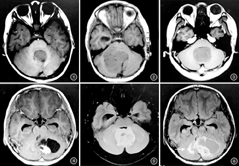

36例髓母细胞瘤均发生于幕下,儿童病灶位于小脑蚓部21例(图1)、小脑半球4例,成人病灶位于小脑半球9例(图2)、小脑蚓部2例,儿童与成年人髓母细胞瘤发生部位差异有统计学意义(P=0.000)。儿童肿瘤最大径为(4.50±0.58)cm,有17例最大径超过4 cm;成年人瘤体最大径为(5.24±1.36)cm,有8例最大径超过4 cm;两组差异无统计学意义(Z=-0.895, P>0.05)。两组患者肿瘤囊变及瘤周水肿情况不同,两组差异均有统计学意义(P=0.034、0.008);而边界、梗阻性脑积水及室管膜种植转移方面组间差异均无统计学意义(P值均>0.05)。见图3,图4,图5,图6及表1。

本组36例患者髓母细胞瘤实性部分均表现为T2WI及T2WI-FLAIR稍高信号,T1WI等偏低信号。其中12例做了DWI检查(5例儿童、7例成人),瘤体实性部分均表现为弥散受限。增强后,两组肿瘤实性区域均表现为轻度至中度强化。

36例髓母细胞瘤均发生于幕下,儿童常见于小脑蚓部(21/25),成人病灶多位于小脑半球(9/11),差异有统计学意义(P=0.000)。儿童肿瘤最大径为(4.50±0.58) cm,其中17例肿瘤最大径超过4 cm;成年人瘤体最大径为(5.24±1.36) cm,其中8例肿瘤最大径超过4 cm;两者比较差异无统计学意义(Z=-0.895, P>0.05)。成人组和儿童组囊变分别有16例和11例,瘤周水肿分别有4例和7例,差异均有统计学意义(P=0.034、0.008);而边界、梗阻性脑积水及室管膜种植转移方面组间差异均无统计学意义(P值均>0.05)。36例患者髓母细胞瘤实性部分均表现为T2WI及T2WI-FLAIR稍高信号,T1WI等偏低信号。12例做了弥散加权成像检查(5例儿童、7例成人),瘤体实性部分均表现为弥散受限;增强后,两组肿瘤实性区域均表现为轻度至中度强化。